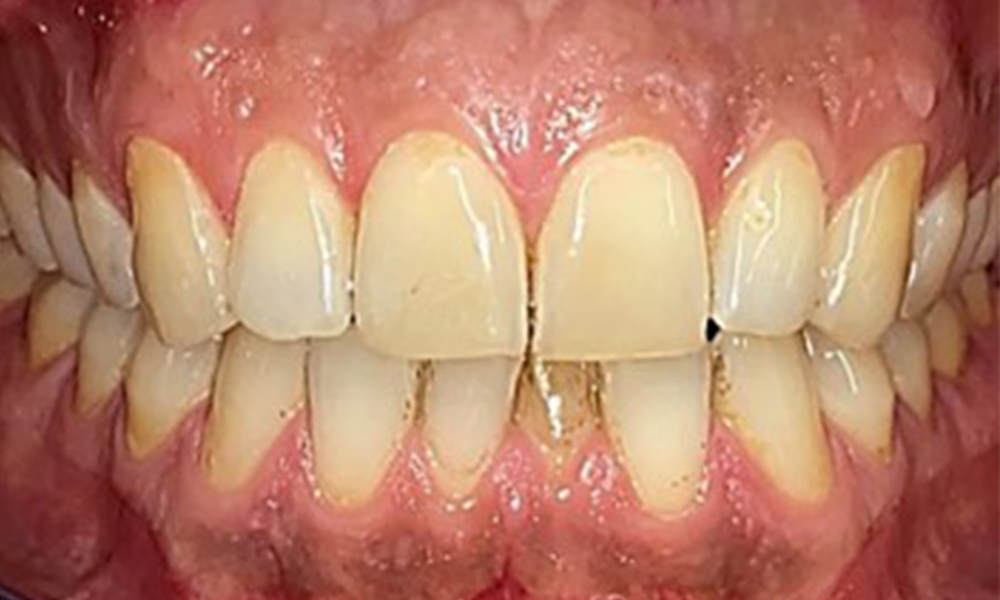

Extraoral sind keine pathologischen Befunde festzustellen, intraoral zeigen sich bei der Frontalansicht im Bereich der keratinisierten Gingiva und am Übergang zur beweglichen Schleimhaut bräunlicheVerfärbungen (Abb. 2), welche auf den Nikotingenuss zurückzuführen sind. Am Gaumenbereich zeigen sich insbesondere im Bereich Oberkiefermolaren palatinal weißliche Schleimhautveränderungen, die ein Hinweis auf einen erhöhten Verhornungsgrad sind und ebenso auf den Nikotingenuss zurückzuführen sind. Die Zunge ist mit einem weiß-bräunlichen abwischbaren Belag versehen.

Frontalansicht

Abb. 2 Frontalansicht, © Dr. R. Krapf